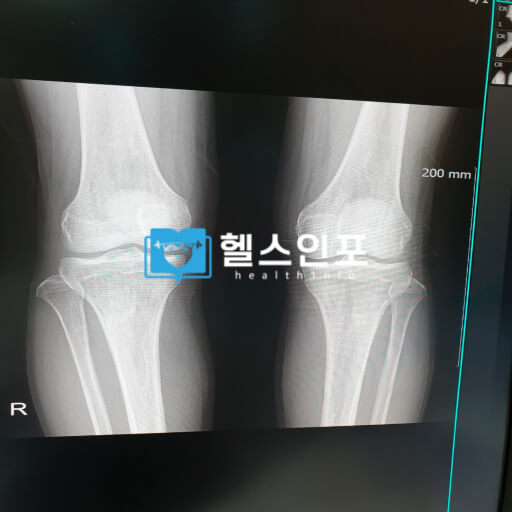

• 뼈 밀도 검사: 50세 이상이거나 골다공증 위험이 있는 경우, 정기적으로 뼈 밀도를 검사받는 것이 좋습니다.